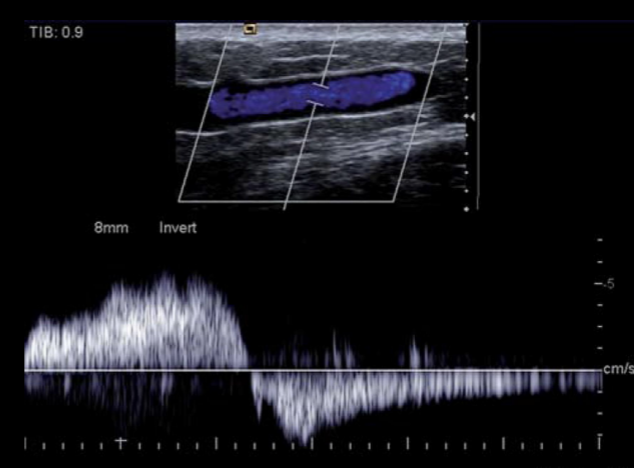

12

A

Dilatación venosa